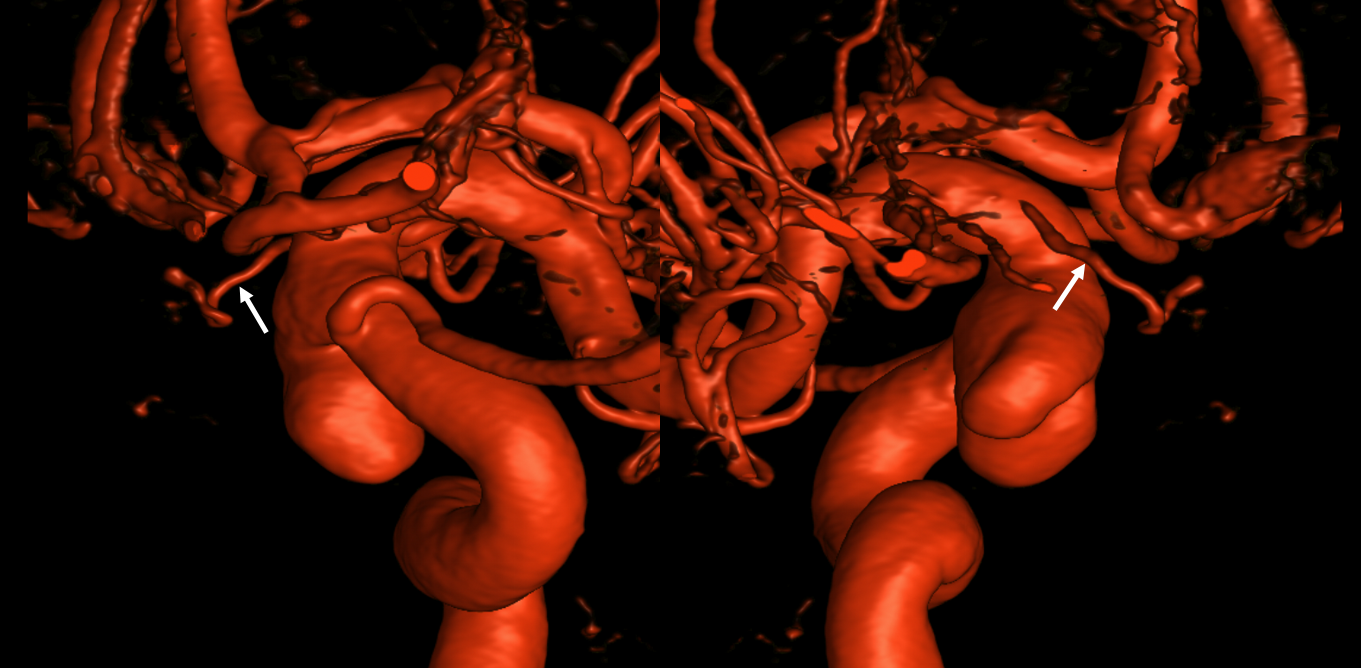

VR — the anterior-most branch of the superior hypophyseals is usually the largest (arrow). The others are too small to see on a VR image

MIPS. The anterior, proximal-most branch (arrow) tends to supply the optic nerve (white oval), while the more posterior branches (dashed arrows), when present, supply more posterior structures such as chiasm and tract (dashed oval)

A highly unusual branch originating from ILT region swings underneath the cavernous ICA and supplies the floor of the pituitary fossa. Yet unknown, as far as i know

More Optic Nerve Supply — its easier to see on MIPS, but with the right windowing, and stereo, VR imaging is also possible. Here, there are 3 superior hypophyseals seen. The anterior-most (arrow) is usually the largest, suppling the optic nerve (dashed arrow) and chiasm (ball arrow). The middle and posterior hypophyseals (arrowheads) supply the stalk.

Stereo of VR image. Same arrows. The stalk is open arrow.

Another patient — also 3 arteries. Cave origin of the anterior-most (arrows) one. The middle one (arrowheads) also supplies the optic nerve. The posterior one (dashed arrows) is for the stalk.

VR images (stereo pair on bottom). The cave origin of the anterior branch is most beautifully seen in the upper right image.